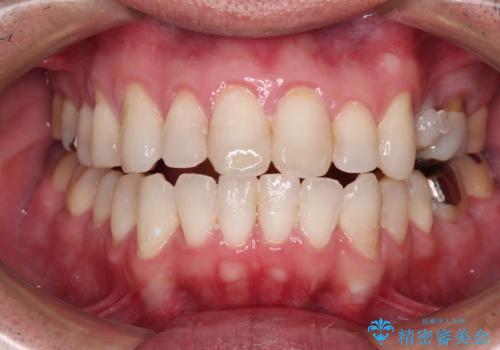

内側に転位した歯とボロボロのむし歯 インビザラインによる矯正治療とむし歯治療

- ボロボロのむし歯とデコボコの歯列を気にして来院された患者様です。

ボロボロとなっていた歯は抜歯が必要な状態でしたが、舌側転位している歯を移動させることで抜歯スペースを埋めることができるため、矯正治療により歯列を整えることとしました。

舌側転位の改善にインビザラインを用いるのはやや難易度が高くなりますが、前歯部のデコボコは軽度であったため、インビザラインによる矯正治療を行うこととしました。

矯正治療後には抜歯が必要な歯に隣接してむし歯となっていた歯をオールセラミッククラウンにて補綴治療を行うこととしました。